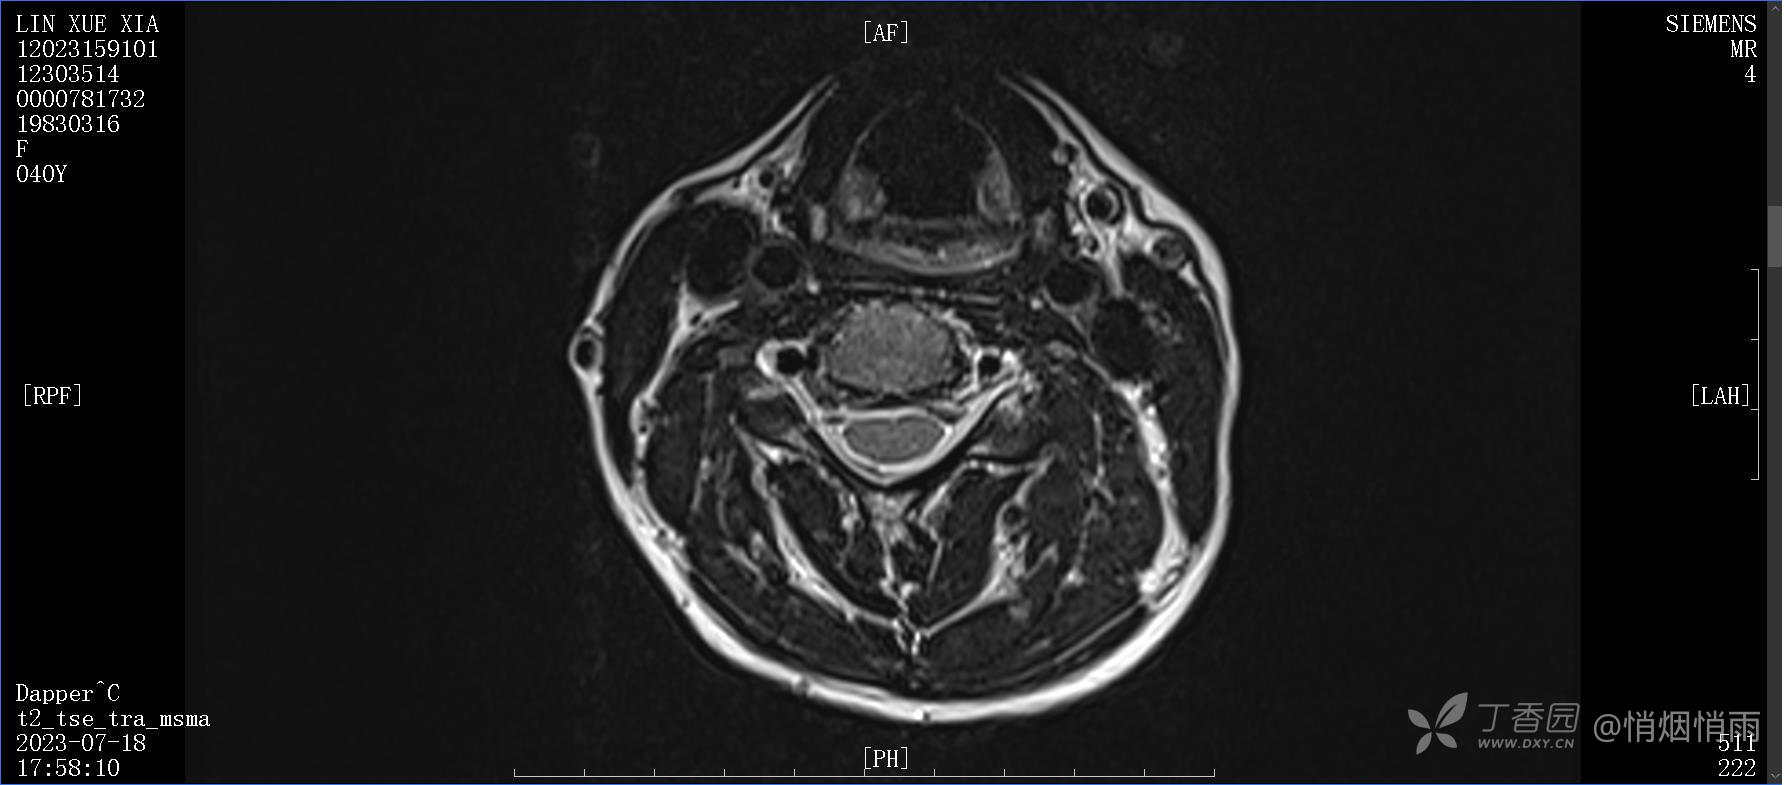

辅助检查:

目前的诊断,暂时依据辅助检查诊为肩袖损伤,但是患者疼痛的性质和特点,却不是单纯的肩袖损伤所致。考虑过胸廓出口综合征,但是该疾病会出现肩胛区的疼痛吗?(由于考虑到费用的问题,没再进行下一步的检查)带状疱疹会有如此的症状吗?